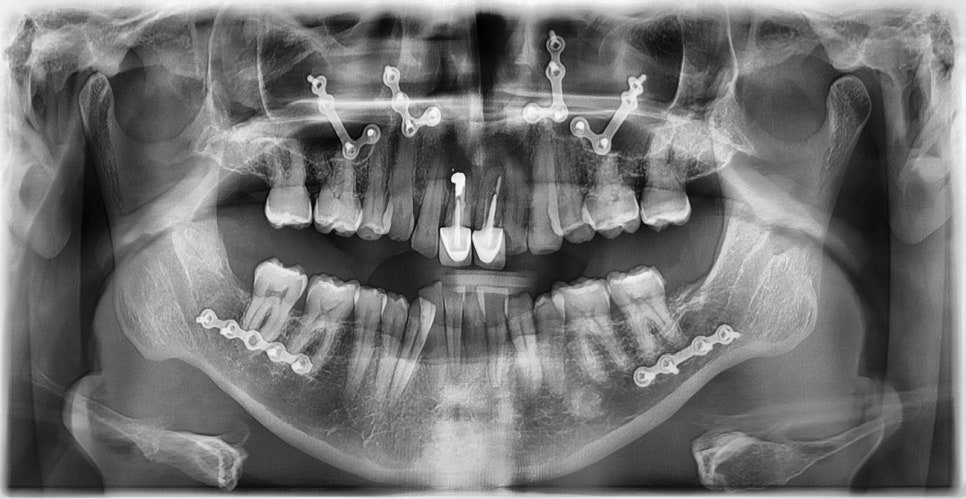

이 환자분은 영국에서 오신 40대 초반 남성분으로, 선천적으로 턱이 작아 어린 시절 턱을 앞으로 이동시키는 악교정 수술과 함께 약 6년 간 치아 교정을 받으셨다고 하셨습니다. 그러나 교정 치료가 충분히 만족스럽게 이루어지지 않았고, 이후 사고로 앞니를 다쳐 보철 치료를 받게 되었습니다. 시간이 지나면서 잇몸이 퇴축되어 앞니 보철물의 금속 부분이 노출되었으며, 제 2급 부정교합 및 불규칙한 치아 배열로 인해 심미적으로 정돈되지 못한 상태로 오랜 기간 지내오셨습니다. 이제는 앞니를 보다 아름답게 개선하고 싶다는 바람으로, 멀리 영국에서 한국까지 내원해 주셨습니다.

2025-11-28 초진 : 연세정원치과

진단 결과, 교합시 하악 전치가 거의 보이지 않을 정도로 깊은 교합을 보이고 있었으며, 어린 시절 외상을 입었던 앞니는 치아 뿌리 부근에 광범위한 염증이 관찰되어 장기적인 유지가 어려운 상태였습니다. 이에 앞니 두 개는 발치를 결정하였고, 환자의 비교적 젊은 나이를 고려하여 가능한 한 최대한 치아를 보존하기 위해 앞니 부위 임플란트를 고려했습니다. 그러나 해당 부위 골 손실이 매우 심했고, 외국인 환자로 장기간 내원이 어려운 상황이었기 때문에, 광범위한 골이식을 동반한 임플란트 치료 보다는 비교적 짧은 기간 내에 기능과 심미를 회복할 수 있는 브릿지 보철 치료를 계획하였습니다.

또한 하악 전치가 혀 쪽으로 과도하게 쓰러져 있어 보철적으로 위치를 회복하기에는 한계가 있어, 발치 후 후 상하악 모두 브릿지 보철로 치료 계획을 수립하였습니다. 하악 전치를 원래 자리에 위치시킬 경우 뼈가 너무 올라와 있었기 때문에, 발치 후 아래 앞니 부위 골성형도 시행하기로 하였습니다.